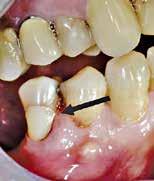

Fig. 15. Patienten blev (uden henvisning) opfordret til at fortsætte behandlingen på universitetstandklinik. Privatpraktiserende tandlæge havde påbegyndt rodkanalbehandling. A. Præoperativ røntgenoptagelse viser rodfyldt mesiofacial kanal. B. Klinisk foto efter fjernelse af midlertidig fyldning viser rodfyldning af MB1 og MB2 kanaler, furkal perforation (pil), instrumenteret distofacial kanal og palatinal kanal, som ikke er instrumenteret/fundet. C. Den furkale perforation blev lukket (pil), og den palatinale kanal blev lokaliseret og udrenset.

Fig. 15. Patient was advised (with no referral) to continue treatment at the University Dental Clinic. First maxillary molar had root canal treatment initiated by private practitioner. A. Preoperative radiograph showing root filled mesio-buccal canal. B. Clinical photo after removal of temporary restoration showing root filled MB1 and MB2 canals, furcation perforation (arrow), instrumented disto-buccal canal and uninstrumented/unlocated palatal canal. C. Furcation perforation was repaired (arrow), palatal canal located and instrumented.